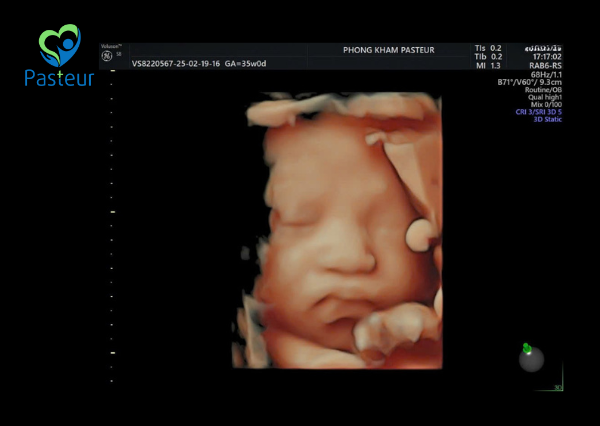

Siêu âm thai 4D là một phương pháp chẩn đoán hình ảnh hiện đại, nâng cấp từ siêu âm 2D và 3D, cho phép quan sát thai nhi trong thời gian thực. Thay vì chỉ hiển thị hình ảnh tĩnh như siêu âm 2D và 3D, siêu âm 4D ghi lại các chuyển động của bé, giúp cha mẹ nhìn thấy những cử chỉ đáng yêu như mút tay, duỗi chân hay nở nụ cười trong bụng mẹ.

Không chỉ mang lại trải nghiệm đầy cảm xúc cho cha mẹ, siêu âm 4D còn giúp bác sĩ đánh giá hình thái thai nhi một cách chi tiết, hỗ trợ phát hiện sớm các bất thường về cấu trúc cơ thể.

- Quan sát thai nhi sống động: Giúp cha mẹ nhìn thấy rõ khuôn mặt, tay chân và các cử động của bé.

- Hình ảnh sắc nét, chân thực – Máy siêu âm công nghệ cao cho độ phân giải tốt, giúp mẹ bầu nhìn rõ từng đường nét khuôn mặt con yêu.